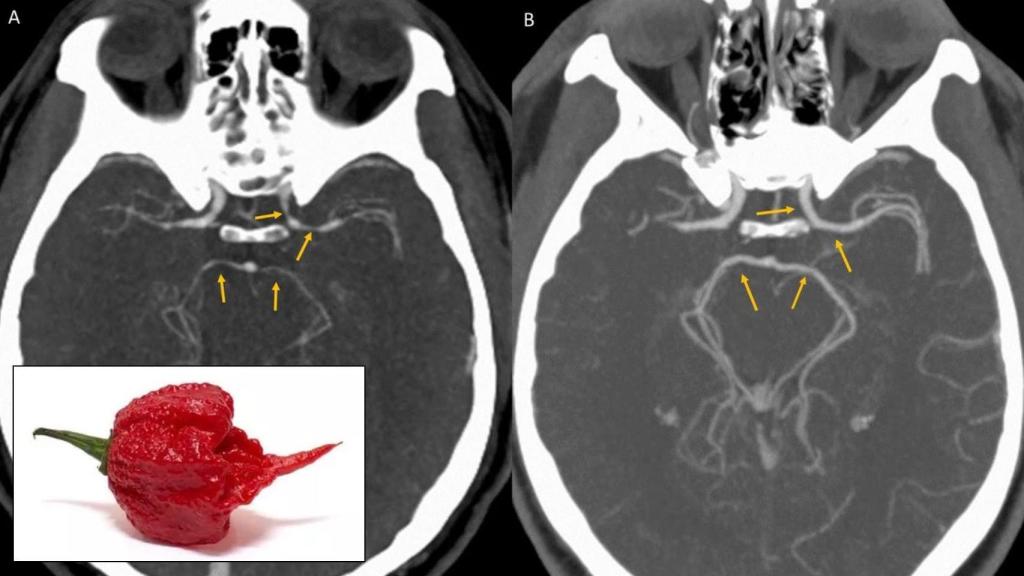

Angiografía que muestra la contracción de las arterias del paciente; en primer plano, el pimiento culpable.

Sin embargo, al analizar más profundamente los resultados de la tomografía computerizada observaron que varios vasos sanguíneos del cerebro se habían estrechado notablemente. Se trata de una afección conocida como síndrome de vasoconstricción reversible, que puede ser provocada tanto por el consumo de medicación como por estupefacientes.

Ya se había asociado el consumo de sustancias muy picantes a la constricción repentina de la arteria coronaria y ataques cardíacos, por lo que parecía muy posible que ésta fuera la causa. Bastó con que pasara un tiempo desde el consumo del pimiento para que todo volviera a la normalidad, como demostraron las pruebas que se le repitieron cinco semanas después.